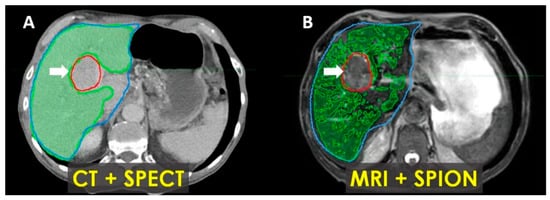

In patients with Child–Pugh A-6 cirrhosis, functional treatment planning using SPION-enhanced MRI-Linac demonstrates superior performance compared to SPECT-CT-based treatment planning, as illustrated in Figure 7.

Early results incorporating functional treatment planning using SPION-enhanced MRI-Linac for liver SBRT demonstrated the effectiveness of this approach for the quantitative characterization of functional liver parenchyma and enhanced tumor visualization [34]. Our findings also suggest that it outperforms SPECT-CT-based treatment planning in cirrhotic patients undergoing liver SBRT (Figure 7).

Figure 7. Patient with Child–Pugh A liver cirrhosis: SPECT-CT (A) and MRI-SPION (B) imaging of tumor (arrow) and functional liver volumes (FLVs) (green). Anatomic liver volume delineated in blue. There is an estimated 20% loss of functional hepatic parenchyma, with more accurate tumor delineation defined via MRI-SPION compared to SPECT/CT.